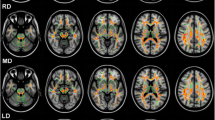

For statistical analysis of the deep grey matter, these structures were set into reference to head size by dividing the volume of the structure by NBV, analogous to the methods used in Ward et al. [32] as presented in Fig. 1. Deep grey matter structures were compared between the boxer and HC groups by applying a multivariate analysis of variance with BMI. Our results were also corrected for effects of age in an analysis of covariance. Linear regression analysis examined the association between number of fights and duration of boxing in years on regional brain volumes of boxers.